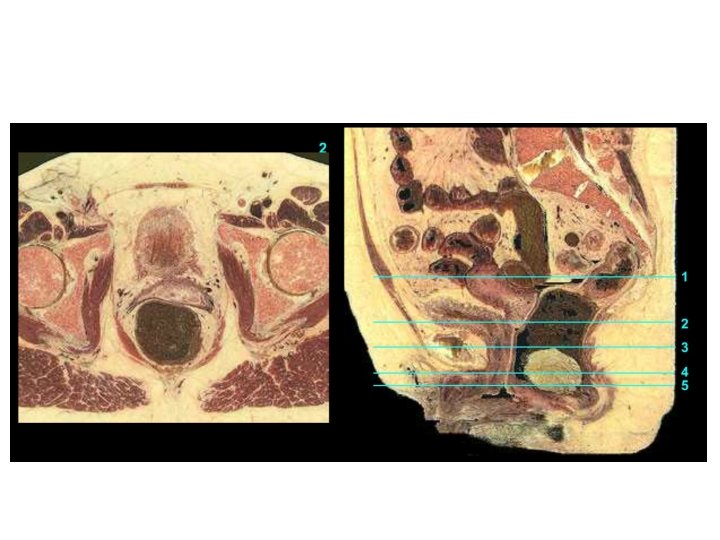

Vagina Excavatio vesicouterina Peritoneum Excavatio rectouterina Uterus Portio vaginalis cervicis Vesica urinaria Portio supravaginalis cervicis Fornix vaginae, Pars posterior Fornix vaginae, Pars anterior Vagina, Paries anterior Rectum Urethra Septum rectovaginale Septum vesicovaginale Vagina, Paries posterior Ostium vaginae Vestibulum vaginae Diaphragma urogenitale